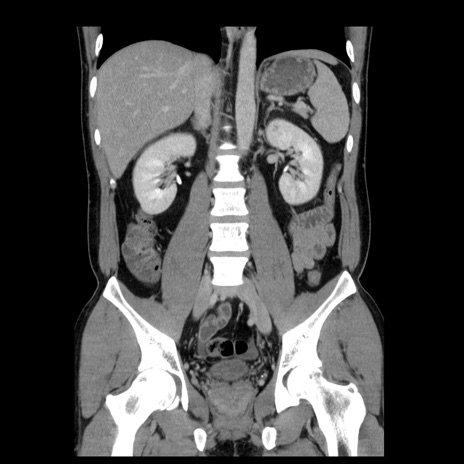

症例4(冠状断像)

【症例】30歳代男性

【主訴】腹痛、嘔吐

【現病歴】昨晩から突然の腹痛あり、その後嘔吐、軟便も出現。腹痛が改善しないため救急搬送となる。2日前にしめ鯖の食事歴あり。

【身体所見】意識清明、苦悶様、BP 135/90mmHg、BT 35.7℃、腹部:平坦、やや硬、心窩部〜臍部に自発痛、圧痛あり、筋性防御+、反跳痛-

【データ】WBC 8100、CRP 0.57